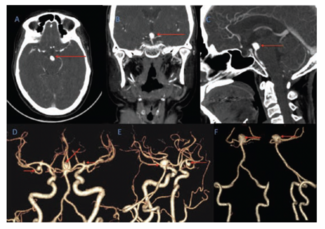

B. Vivek Joseph, FRCSI, MCh; Tufail Patankar, MBBS, DMRD, DMRE, DNBE, FRCR, PhD; Santhosh Babu Bharathy, MD, MBBS; Vinu Moses, MD, DNB, MBBS; Shyamkumar Nidugala Keshava, MBBS, DMRD, DNB, FRCR, FRANZCR

This case report presents the details of a patient with a wide-necked basilar top aneurysm, ruptured 1 month earlier, which was managed using a new endosaccular device, Neqstent.